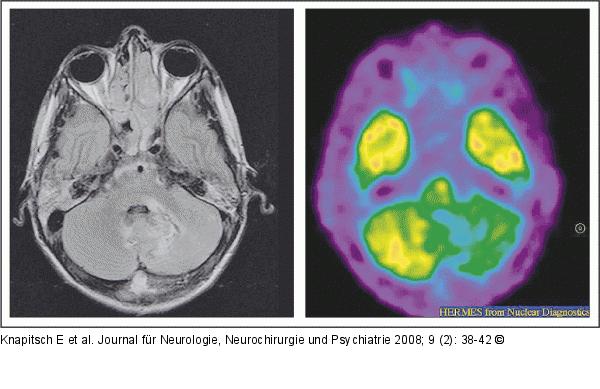

Abbildung 4: FPS Positronen-Emissions-Tomographie (PET) nach i.v.-Applikation von 370 MBq 18F-Fluor-Deoxyglykose (FDG): Substanzdefekt linkscerebellär. |

Positronen-Emissions-Tomographie (PET) nach i.v.-Applikation von 370 MBq 18F-Fluor-Deoxyglykose (FDG): Substanzdefekt linkscerebellär. |